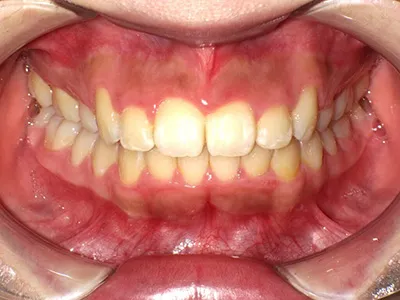

症例4

before

after

| 主訴 | 八重歯が気になる、歯並びきれいにしたい |

|---|---|

| 治療内容 | ワイヤー矯正 |

| 治療期間 | 1年 |

| 費用 | 770,000円(税込) |

| リスク・副作用 | 歯牙移動による痛み、染みる症状が出てしまうことがあります |